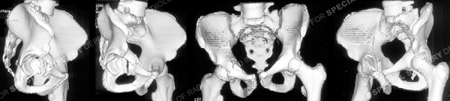

3 dimensional CT reconstructions